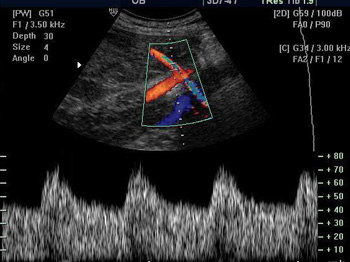

- Импульсно-волновой/постоянно-волновой доплер PWD/CWD

Постоянно-волновой доплер. Благодаря данной функции вы сможете проводить количественную оценку кровотока в сосудах с высокоскоростными потоками, что активно используется в исследованиях эхокардиографии